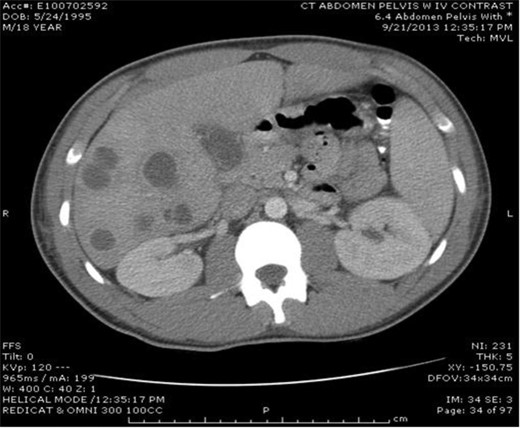

An 18-year-old, previously healthy college student presented to our hospital with a chief complaint of abdominal pain. He also reported 4 days of high-grade fevers, nausea and emesis. A computed tomography scan of the abdomen with IV contrast at an outside institution showed multiple hepatic abscesses (Fig. 1). Aside from several days of upper respiratory symptoms and odynophagia, a review of systems was negative. He denied any alcohol, illicit drug or tobacco use. On initial examination, the patient was tachycardic, normotensive and febrile to 39.2°C. Aside from minimal right upper quadrant tenderness, the remainder of the physical examination was normal. He had no dental disease. Laboratory data showed leukocytosis of 25 000/µl, erythrocyte sedimentation rate (ESR) 66, International Normalized Ratio 1.41, aspartate transaminase 32, alanine transaminase 50, alkaline phosphatase 147 and direct bilirubin 0.5. A transthoracic echocardiogram showed no valvular lesions.

Multiple lucencies noted within the liver consistent with abscesses along with a thickened gallbladder.